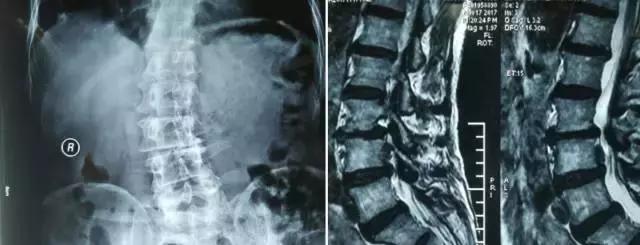

术前影像学检查:

X片报告:腰椎侧弯

MRI报告:L3-4椎间盘突出;L4-5及L5S1椎间盘膨出

3D CT报告:L3-4椎间盘左后方脱出,压迫硬膜囊及左侧神经根,左侧侧隐窝狭窄; L4-5及L5S1椎间盘膨出,双侧侧隐窝狭窄